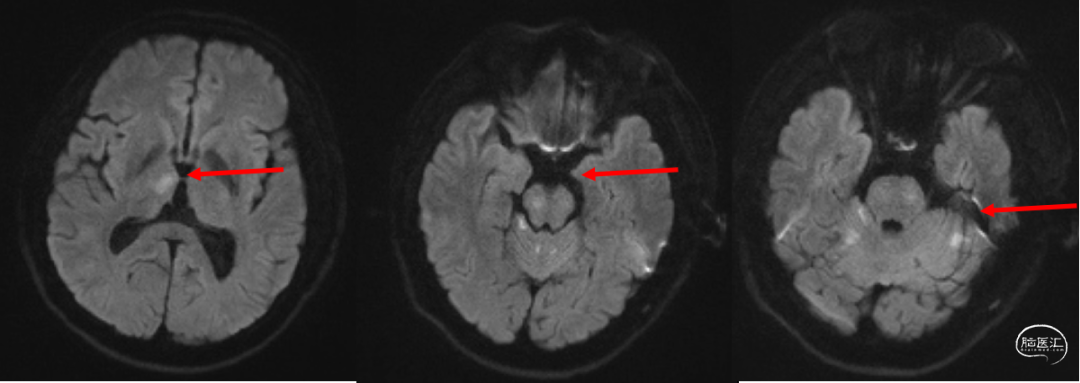

术前影像学检查

头颅MRI+MRA(入院27分钟):右侧丘脑、脑干及双侧小脑半球急性梗死可能;左侧基底节区软化灶;双侧大脑后动脉及基底动脉纤细,局部显示欠清。